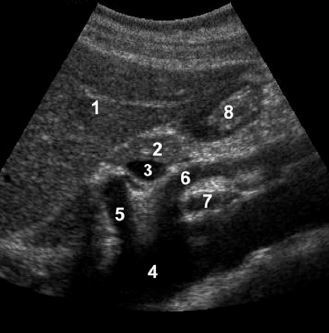

A

1. left lobe of liver

2. pancreas

3. porto-splenic confluence

4. aorta

5. IVC

6. SMA

7. CBD

8. gastroduodenal artery

The CBD travels in the most posterior aspect of the

pancreas. In fact, it often appears immediately anterior

to the IVC. The gastroduodenal artery arises from the

common hepatic artery and descends along the anterior

aspect of the head of the pancreas. These two structures

often appear as two small anechoic dots on transverse

views of the pancreatic head.